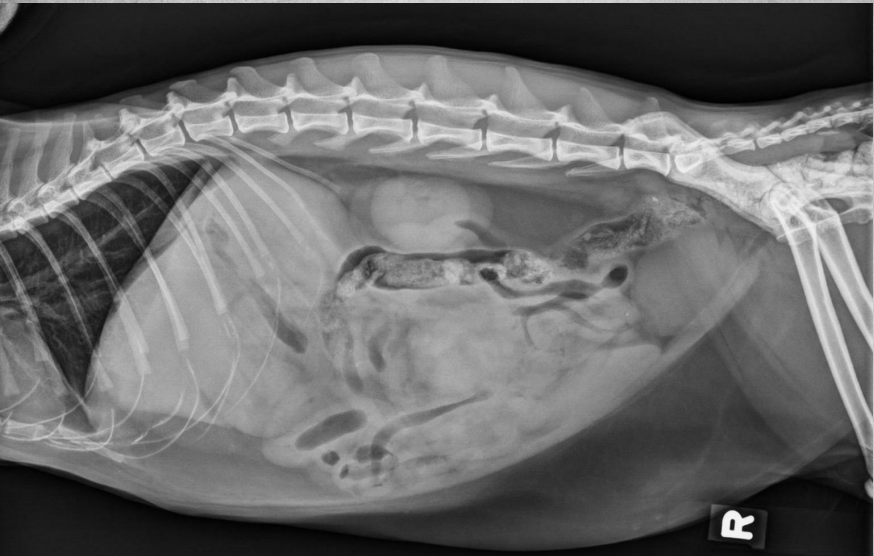

●9 yo mixed breed female dog

(sterilized)

●Increased ALP

● Impressive amount of subcutaneous and intra-abdominal fat.

● Enlarged liver – changed gastric axis pushed caudally, rounded edges, extending past the costal arch.

● At least two round soft tissue opacity structures superimposed on ventral liver (lateral view).

● Round soft tissue structure cranial to right kidney.

● Mass in adrenal gland or pancreas

● Hepatic nodules (benign vs metastatic disease)

SI gas is normal because bowels empty.